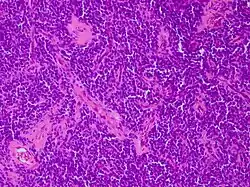

| Micrograph of an H&E stained section of a peripheral PNET. | |

It is classified into two types, based on location in the body: peripheral PNET and CNS PNET.

Peripheral PNET

The peripheral PNET (pPNET) is now thought to be virtually identical to Ewing sarcoma:

"Current evidence indicates that both Ewing's sarcoma and PNET have a similar neural phenotype and, because they share an identical chromosome translocation, they should be viewed as the same tumor, differing only in their degree of neural differentiation. Tumors that demonstrate neural differentiation by light microscopy, immunohistochemistry, or electron microscopy have been traditionally labeled PNETs, and those that are undifferentiated by these analyses have been diagnosed as Ewing's sarcoma."[5]